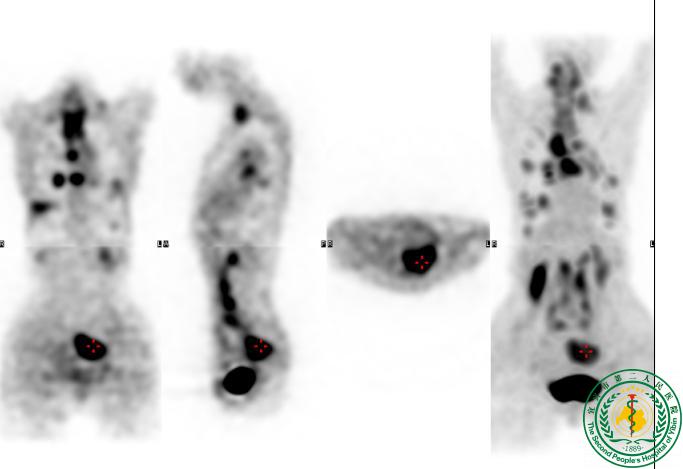

“鹰眼PET/CT”发现结肠Ca术后多处转移一例

“鹰眼PET/CT”发现结肠Ca术后多处转移一例6508

宜宾市第二人民医院 图文